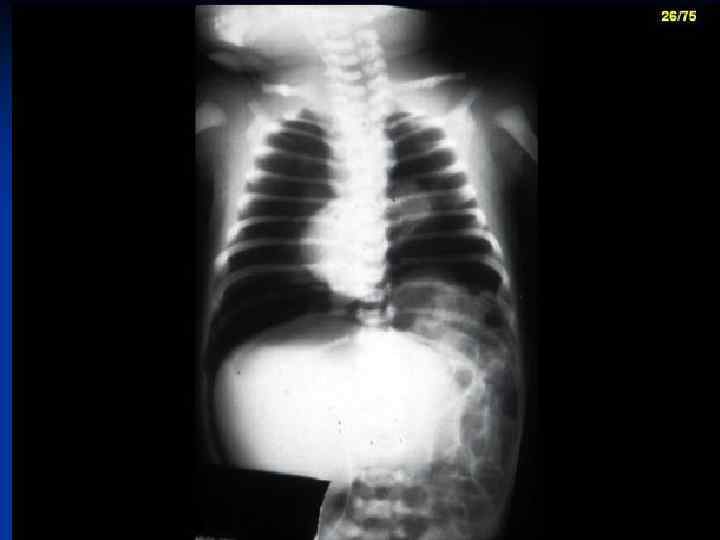

CDH